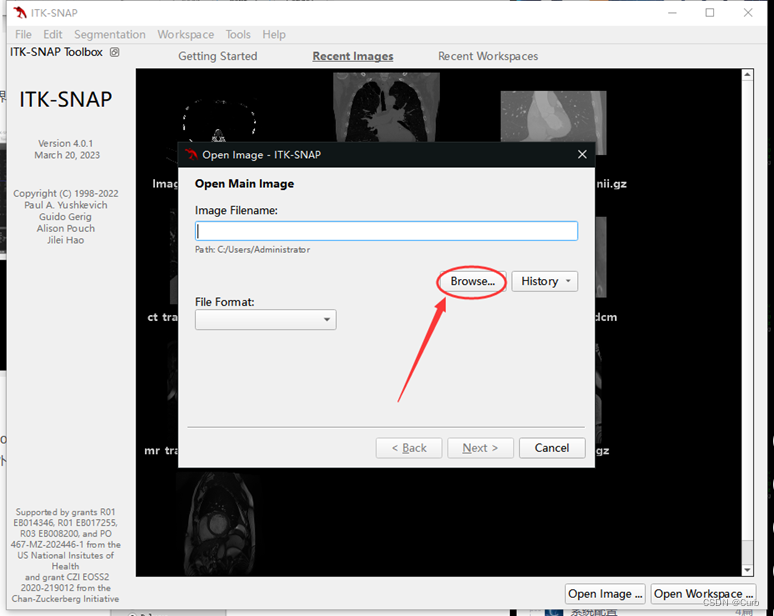

2 导入病例文件

方法一:

再点击“open main image”

打开相应文件路径下的 .dcm 文件即可(一个病例对应多个dcm文件,打开任意一个就会对应打开这个病例的所有dcm)